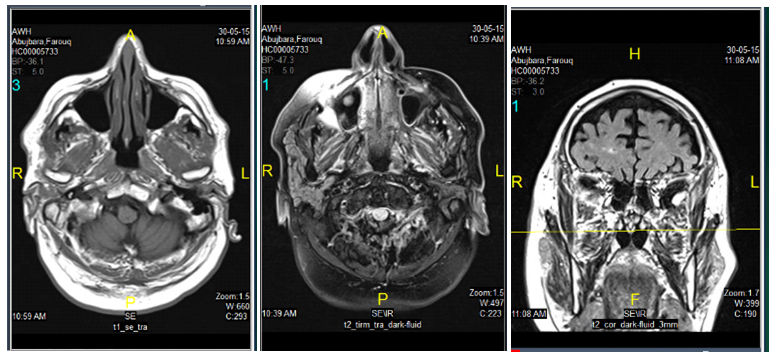

We report the case of a 74-year-old Asian man who suffered complete anosmia from a severe head and nose trauma complicated by epistaxis following sudden fall to the ground after slipping on the steps without loss of consciousness.The patient is a known case of pre diabetes, obesity, hypertension and chronic heavy smoker. . Four weeks later post fall the patient started having a gradual hypogeusia, loosing (salty, sore and sweet sensation.) followed by complete hypogeusia and anosmia over one month period. One month Post fall he was seen by the ENT specialist at another primary health care center who prescribed him intranasal steroid impregnated gauze packing and anti-histamine tablets and instructed the patient to apply topical steroid lotion to his nasal mucosa on a daily basis for one month using a cotton bud. At follow up the patient reported no improvement .Consequently the patient quality of life significantly decreased. Subsequently he was referred to an ENT consultant at the secondary hospital who prescribed him prednisolone 30 mg daily and cetirizine 10mg for one month along with intranasal mometasone spray along with a neurologist who ordered an MRI for the patient showing nasal septal deviation but no fracture or intracranial lesions. This approach also did not improve the patient sense of taste or smell. The patient was feeling down for 12 months and subsequently he visited a consultant family physician with special interest in the use of natural honey who suggested the use of intranasal application of natural honey as a last resort.

The MRI of the patient show no sign of either degenerative disease or conductive olfactory loss due to obstruction, injury of the olfactory cleft, or sinunasal disease.